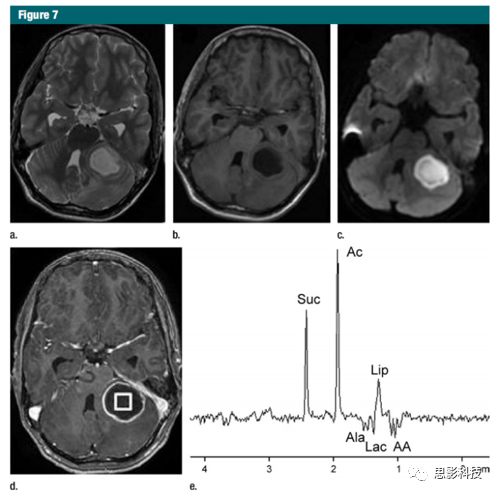

由感染性病原體引起的局灶性病變

腦部感染可能危及生命,因此需要早期診斷以實(shí)現(xiàn)最佳臨床管理。明確的實(shí)驗(yàn)室診斷測試可能很耗時(shí),因此會(huì)延遲治療。磁共振波譜在顱內(nèi)環(huán)增生性病變的鑒別診斷中很有價(jià)值。當(dāng)環(huán)形增生性病變表現(xiàn)出非特異性的臨床和常規(guī)MR影像學(xué)特征時(shí),1H MR波譜可以幫助確認(rèn)化膿性膿腫的明確診斷,并提供有關(guān)感染劑類型的信息。琥珀酸鹽,乙酸鹽,丙氨酸,亮氨酸,異亮氨酸和纈氨酸的表現(xiàn)被認(rèn)為是化膿性膿腫的特異性表現(xiàn)(圖7),即使在MR成像中擴(kuò)散率沒有降低的情況下也是如此。同樣,寄生性囊腫在沒有氨基酸的情況下也含有琥珀酸鹽和乙酸鹽,這有助于將它們與厭氧性膿腫區(qū)分開來。MR波譜學(xué)有助于鑒別結(jié)核性瘤與其他非結(jié)核性病變的區(qū)別,后者在常規(guī)MR成像中具有相似的外觀。結(jié)核性膿腫體內(nèi)1H MR譜僅顯示Lac和脂質(zhì)信號,不含胞質(zhì)氨基酸。磁化轉(zhuǎn)移比磁共振成像和1H磁共振波譜中的氨基酸信號有助于區(qū)分化膿性和結(jié)核性膿腫。因此,MR波譜學(xué)在局灶性腦感染的診斷和臨床治療中起著重要作用。

7:小腦化膿性膿腫的1H MR譜;

a)軸向T2加權(quán)圖像顯示清晰明確的高信號病灶并伴有低血脂壁。

b)軸向T1加權(quán)圖像顯示低等病變伴等強(qiáng)度壁。

c)彌散加權(quán)圖像顯示病變中彌散受限。

d)對比后T1加權(quán)圖像顯示出環(huán)增強(qiáng)。

e)病灶中心的體內(nèi)1H-MR譜圖(3.0 T,PRESS,3000/144,128重復(fù))顯示氨基酸(AA0.9 ppm),脂質(zhì)(Lip)和Lac1.3 ppm),丙氨酸(Ala,1.5ppm),乙酸鹽(Ac,1.9ppm)和琥珀酸酯(Suc,2.4ppm)的共振。